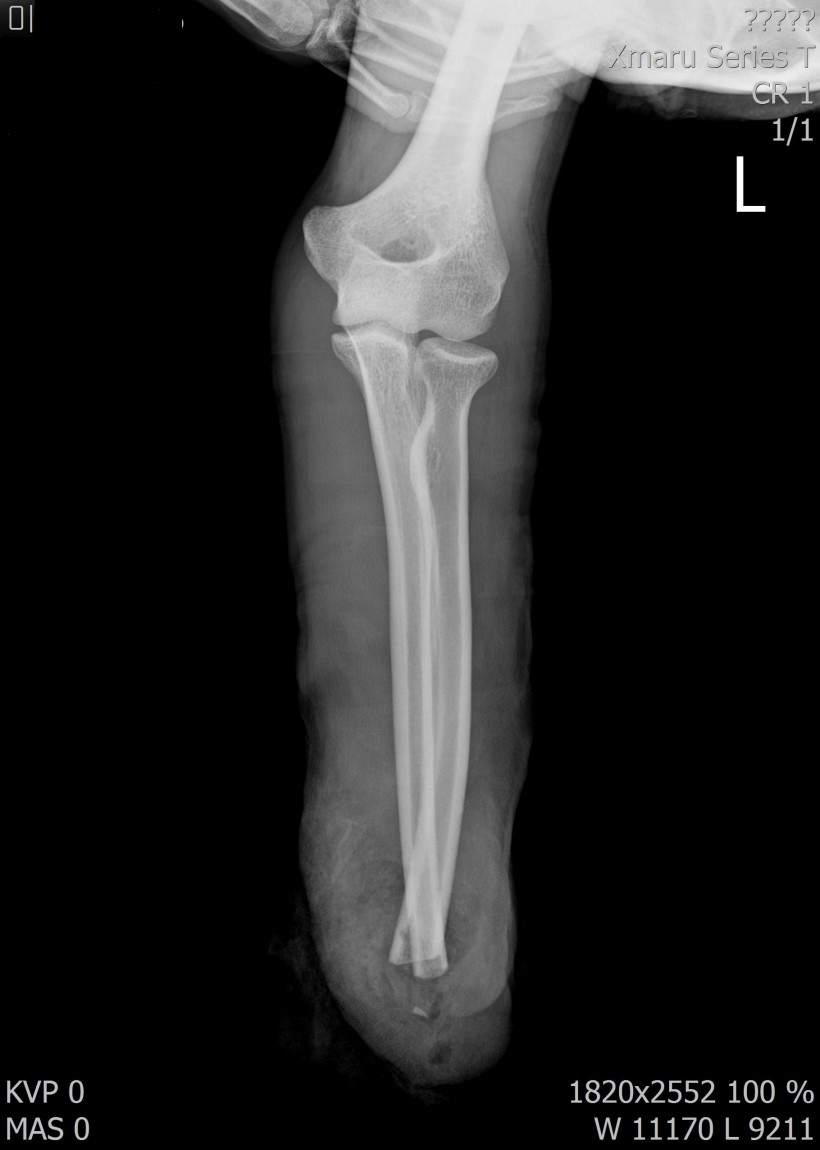

2017년 12월 23일 좌측 손목 절단 ( 치료 과정 모습)

20171223일 당시 ( 외국인 미 **)께서 좌측 손목 전달되어 본원 방문함.

2018.115일 현재 치료 중인 환자에 대하여 .....